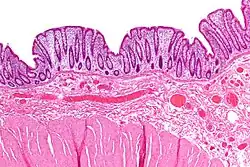

Micrograph showing a rectal wall with changes seen in rectal prolapse. There is a marked increase of fibrous tissue in the submucosa and fibrous tissue +/- smooth muscle hyperplasia in the lamina propria. H&E stain

The precise cause is unknown,[3][10][9] and has been much debated.[5] In 1912 Moschcowitz proposed that rectal prolapse was a sliding hernia through a pelvic fascial defect.[10]